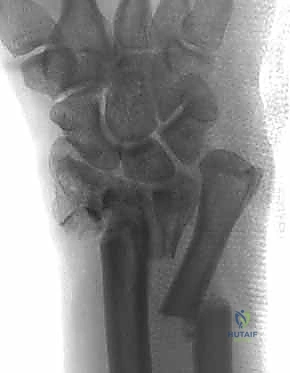

- الأشعة السينية (X-rays):

هي الخطوة الأولى لتقييم الكسر. يتم أخذ صور من زوايا متعددة (أمامية خلفية، جانبية، ومائلة) لتحديد موقع الكسر الأساسي ودرجة الانزياح والتقصير في عظم الكعبرة.

- التصوير المقطعي المحوسب (CT Scan) مع إعادة البناء ثلاثي الأبعاد:

هذا هو المعيار الذهبي الذي يعتمده الدكتور هطيف لجميع كسور المفصل المعقدة. تتيح الأشعة المقطعية رؤية كل شظية عظمية بوضوح تام، وتحديد حجمها، وموقعها، ودرجة تفتت السطح المفصلي بدقة ملليمترية. من خلال إعادة البناء ثلاثي الأبعاد (3D Reconstruction)، يمكن للدكتور هطيف "رؤية" الكسر من جميع الزوايا قبل فتح الجلد، مما يسمح له باختيار الغرسات (الصفائح والمسامير) الدقيقة لكل شظية وتحديد المداخل الجراحية المثلى.